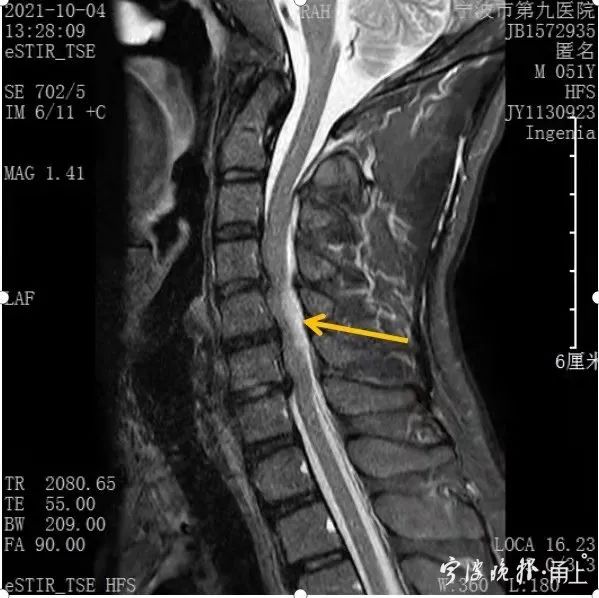

浙江男子肩颈疼痛 2小时后全身失去知觉 医生 严重可瞬间致命 全网搜